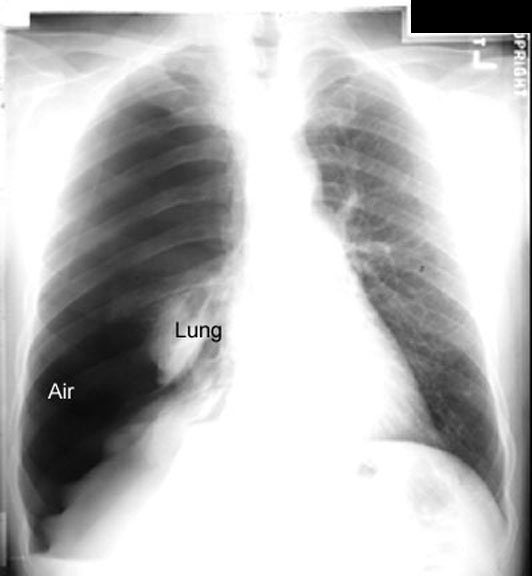

Relaxation Atelectasis The lung is held in apposition to the chest wall because of negative pressure in the pleura. When the negative pressure is lost, as in pneumothorax or pleural effusion, the lung relaxes to its atelectatic position. The atelectasis is a secondary event. The pleural problem is primary and dictates other radiological findings. |